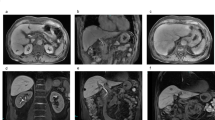

Grayscale US videos of 76 patients with hepatic hemangioma were saved from June 2018 through May 2019. The eligibility criteria were as follows: age ≥ 18 years, ability to hold their breath, and potential for acquisition of a clear grayscale US video. Finally, we enrolled 62 patients who had confirmed diagnoses and could be analyzed with Fluctuational Imaging software. Diagnosis of hepatic hemangioma was confirmed by contrast-enhanced US (21 patients), contrast-enhanced computed tomography (17 patients), or magnetic resonance imaging (4 patients), or by typical appearance on US and absence of changes in morphology and size of the lesion for more than 1 year (20 patients).

Fluctuational Imaging software analysis results were positive for “fluttering sign” in 38 hepatic hemangiomas. Figures 1, 2 and 3 shows the results for Supplementary video V1, Supplementary video V2, and Supplementary video V3, respectively.